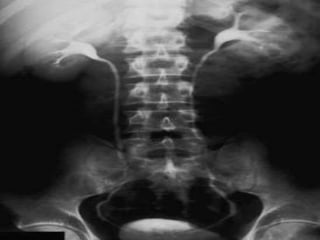

 El centrado de la posición será desde

el pubis, todo hacia arriba, en una

placa 35x43.

Radiografía a los 5 min.

 Debe mostrar los riñones opacificados.

 Ver forma, tamaño y posición.

 Examinar contornos de los riñones: si no es liso,

cualquier irregularidad puede indicar un cicatriz o

una masa.